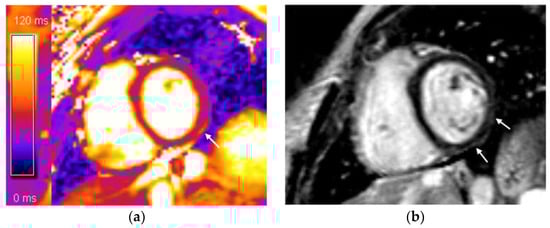

2.2. Cardiac MRI: Protocol and Image Analysis